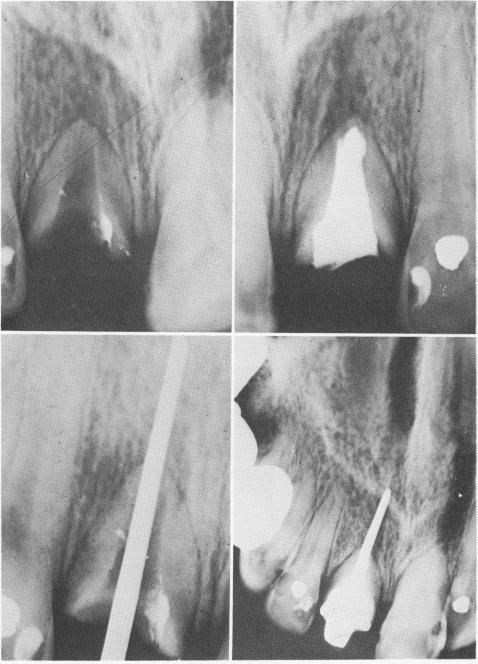

Fig. 13-17. Lengthening a short root to accept a restoration. A, An extremely short root on a central incisor prevented a retentive fitting post crown. B, The short root was first prepared and filled with Kri I paste. C, The Virilium post was fitted and cemented. D, the tooth was still functioning more than 4 years later. (Courtesy H. G. Orlay.)

B

D